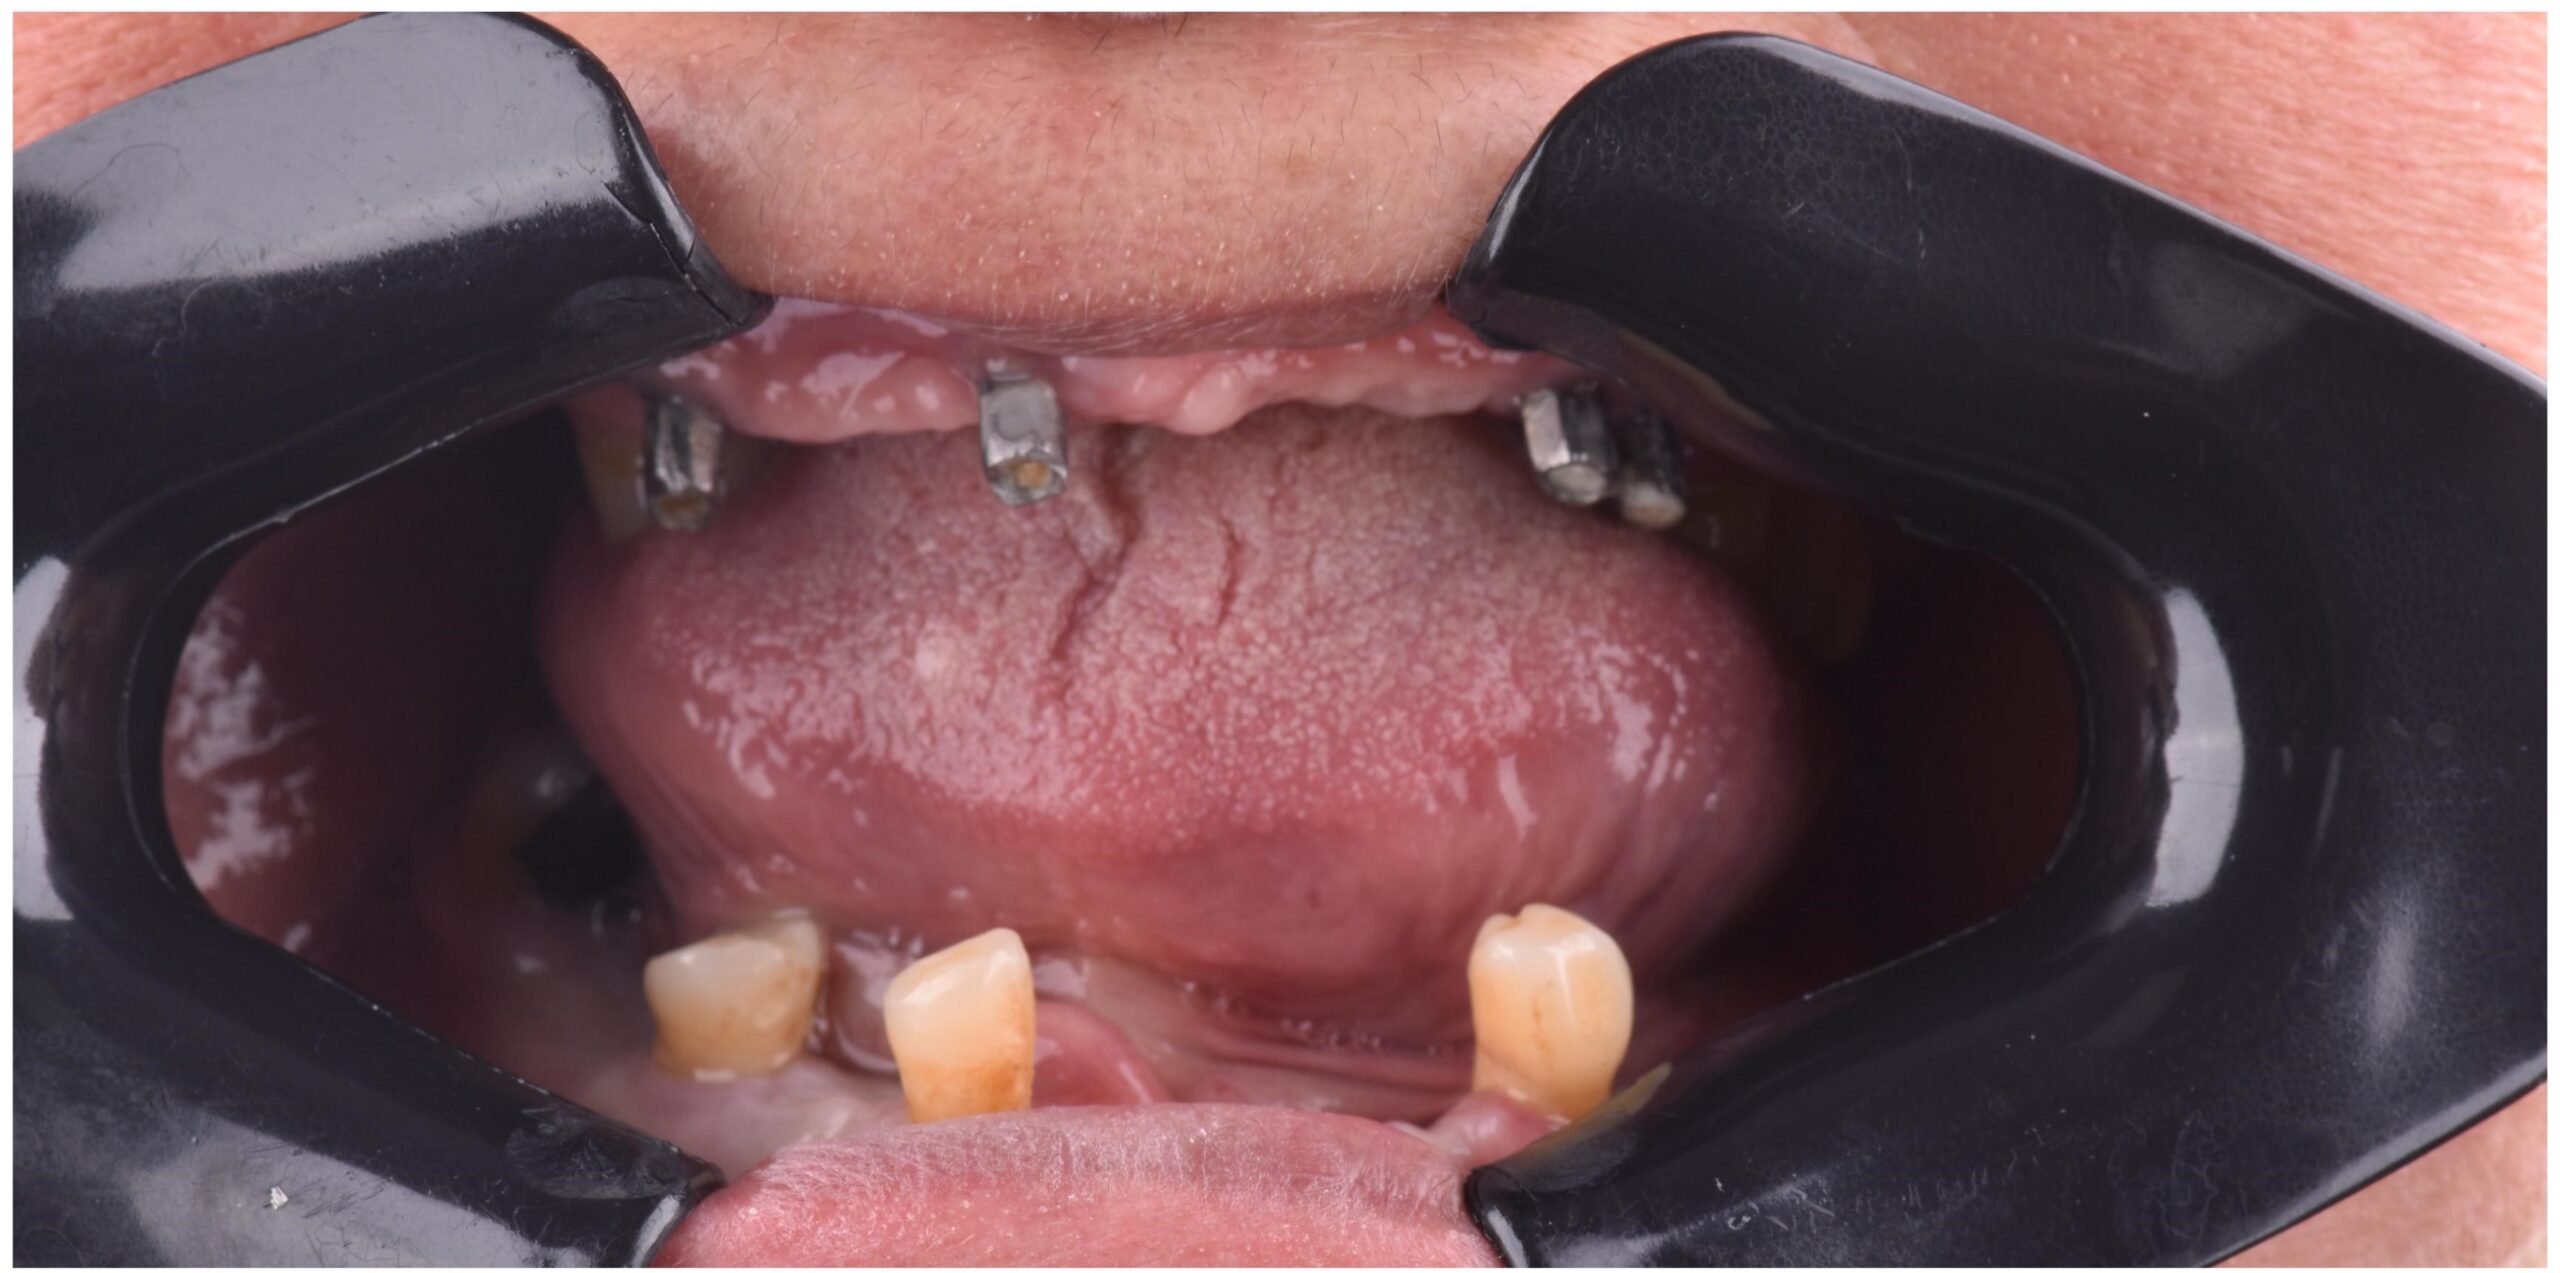

Our Work